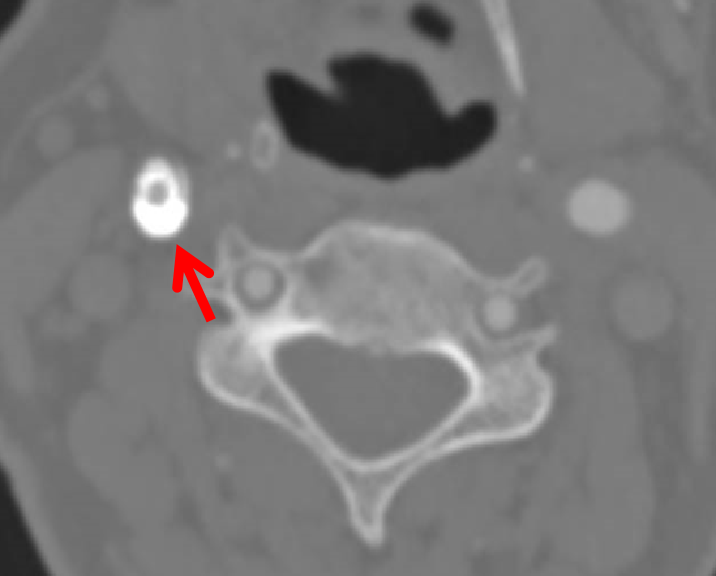

造影血流形态、残余狭窄均可以接受,切线位造影时发现有支架丝伸入到管腔,这样有可能造成涡流,发生内皮损伤,导致支架内再狭窄。这种情况做球囊后扩张,效果可能更好。

这是一个取支架的病例,支架内再狭窄,支架膨胀不全。贴近颈内动脉远端的支架里很光滑,从最后一幅图看,最狭窄处内膜增生严重。这是因为局部涡流形成,导致支架内再狭窄。